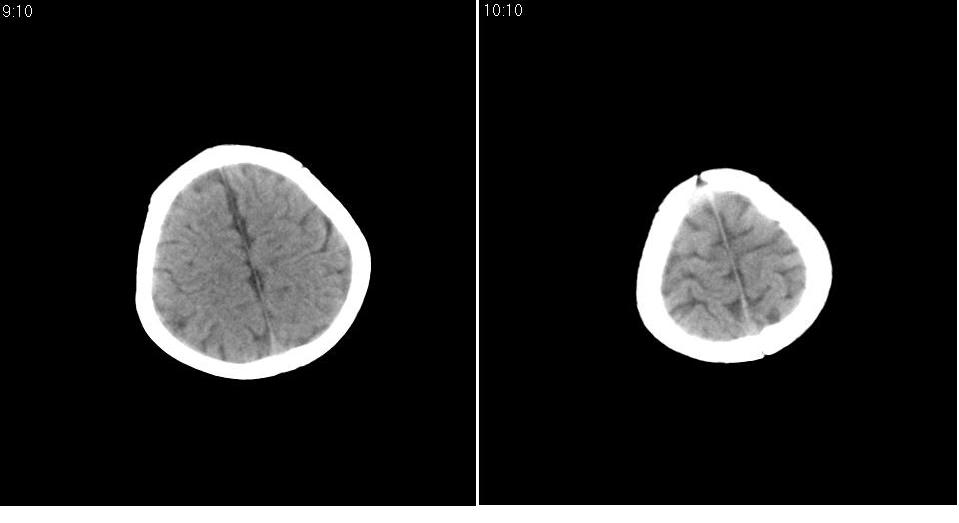

男 1岁,外伤就诊。智力正常,骨窗正常。

正常变异,大枕大池。鉴别:蛛网膜囊肿、双侧小脑发育不良。

蛛网膜囊肿一般是封闭的空间,张力较大,临近颅骨一般受压变薄。本例支持大枕大池

大枕大池与蛛网膜囊肿的主要区别就是看颅骨有没有压迹,如果有的话一般考虑蛛网膜囊肿。

鉴别于巨大枕大池与枕大池区蛛网膜囊肿之间。